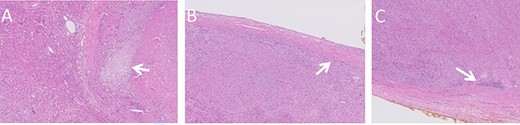

Histologic images of the resected lesion including IVC segment. (A) H&E staining, X20 magnification, demonstrating cells showing cytological atypia with areas of necrosis (arrow). (B + C) H&E staining, X20 magnifications, showing the tumour adjacent and originating from the IVC.

Macroscopic examination of the resected specimen observed a 1.92 kg liver lesion, measured 11x15x23cm. Attached blood vessels could not be separated from said lesion. Histologic examination revealed the diagnosis of a high grade leiomyosarcoma, with wide areas of necrosis, focally prominent cytological atypia and mitotic activity. Immunostains were diffusely positive for Calponin, Desmin, SMA and negative for Myogenin, CD34, S100, CAM5.2 and AE1/AE3. The tumour originates from a large venous type blood vessel – The IVC (Fig. 4). Inked resection margins were free of tumour.